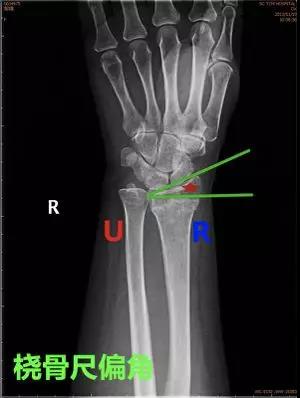

- 桡骨尺偏角:在桡骨、尺骨的下尺桡关节面作一水平线,此线与桡骨远端关节面的切线所形成的夹角。

- 正常值:20°~25°

- 临床意义:若桡骨尺偏角改变,提示腕关节脱位或者桡骨远端骨折。